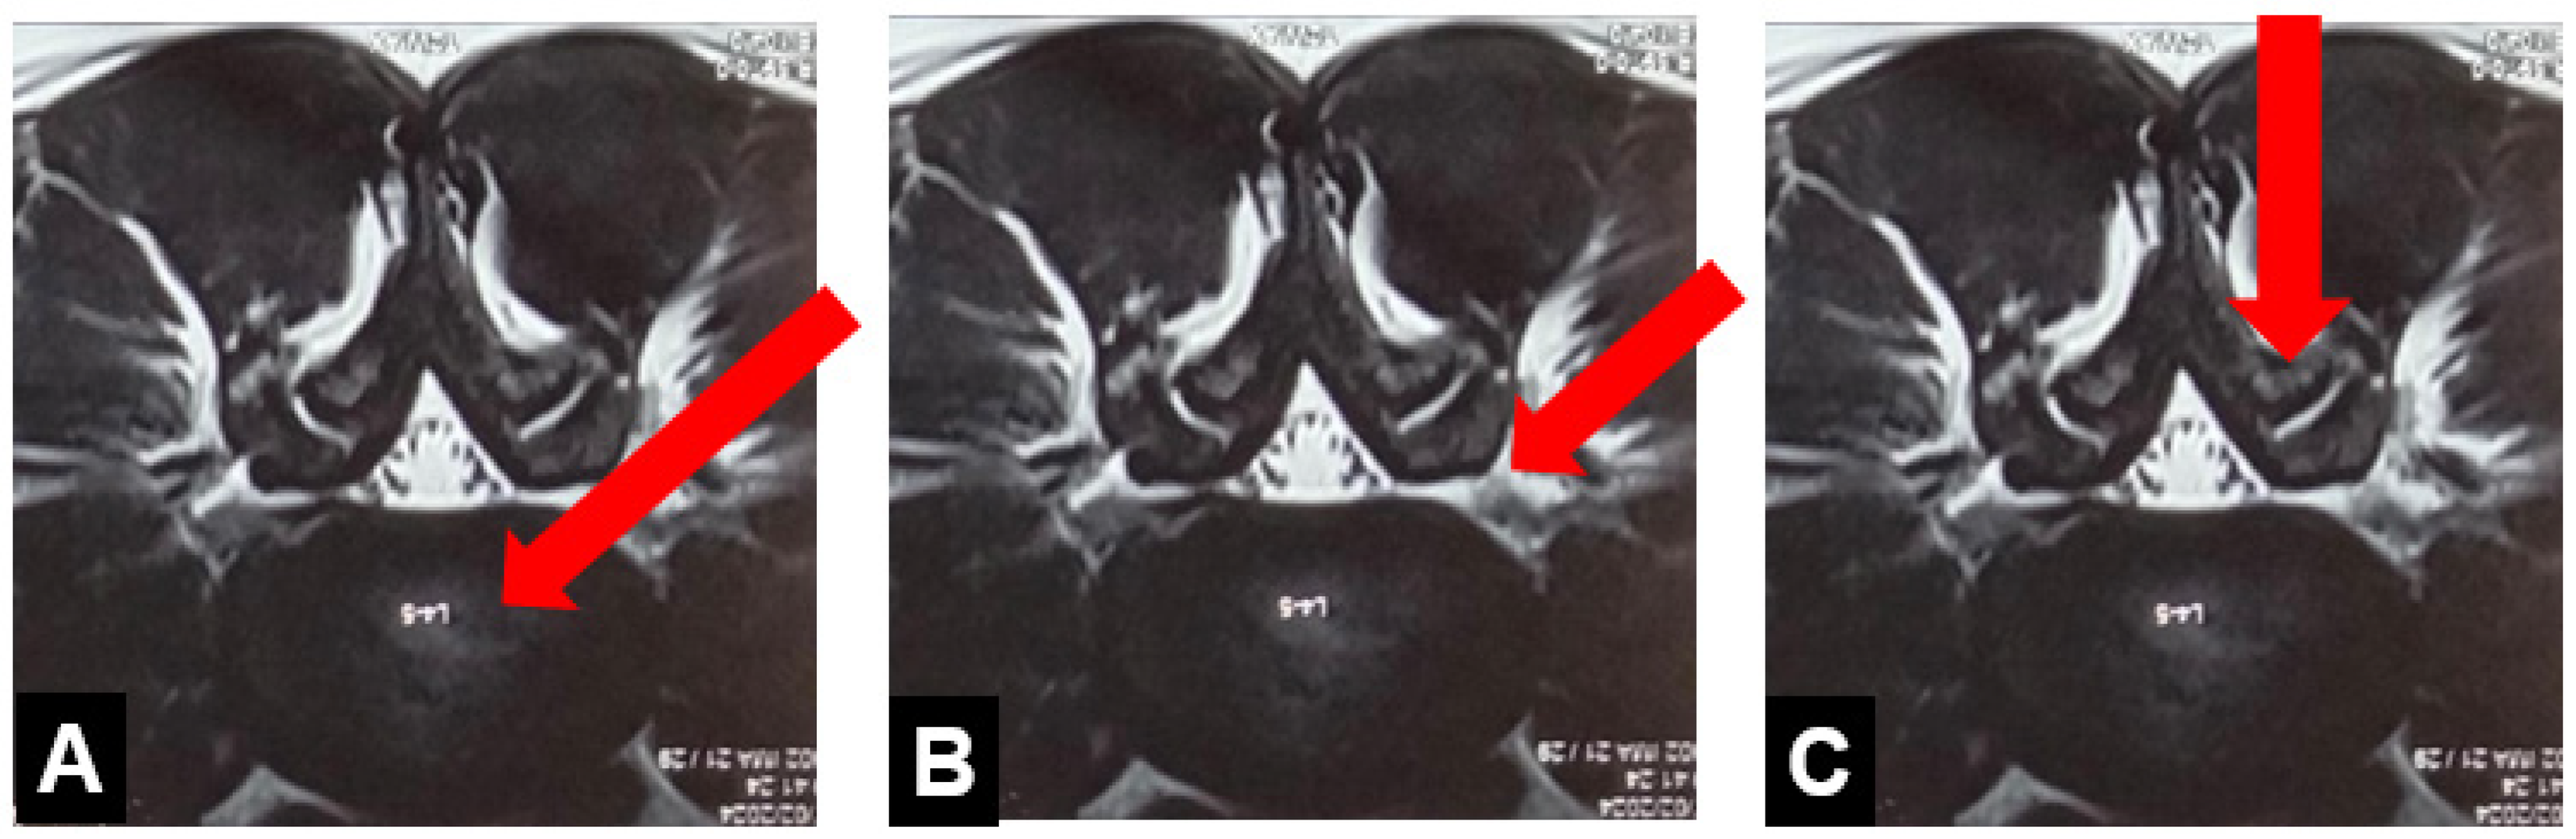

3.4.2. Percutaneous Biportal Endoscopic Discectomy and Decompression (PBED)

3.4.3. Endoscopic Lumbar Interbody Fusion